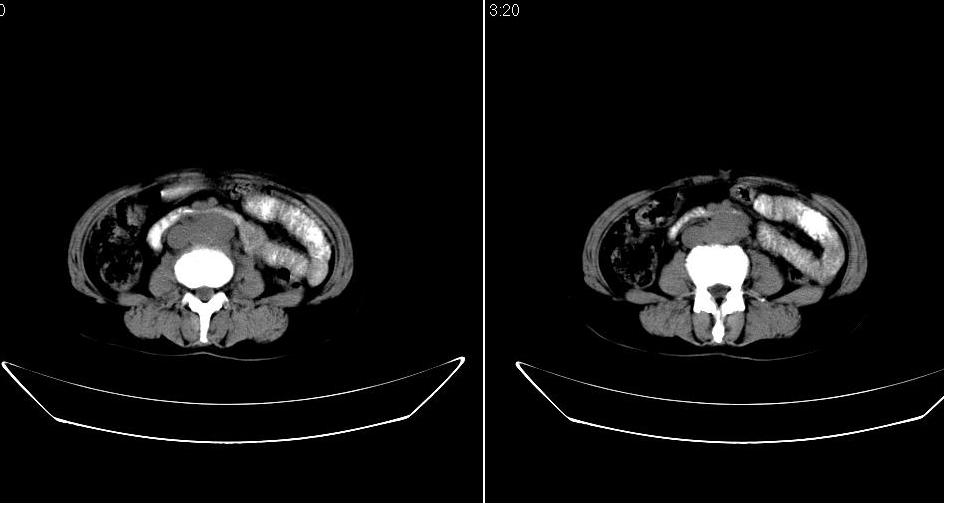

女 53岁,大便每天四到五次,变细,伴有粘液,病人家属说,去年五月在外院行子宫肌瘤术。

腹膜后多发肿大淋巴结肿大并融合改变;右侧回盲部可见团块样软组织影,不规则;

淋巴瘤?回盲部占位,,淋巴瘤肠道改变?建议进一步检查.

腹膜后诸多淋巴结,右侧髂窝软组织块影,综合患者大便次数、形状改变,考虑结肠回盲部肿瘤

回盲部可见团块样软组织影,不规则;腹膜后多发肿大淋巴结肿大并融合改变;考虑回盲部肿瘤并腹膜后淋巴结转移,建议钡剂灌肠或增强检查.

双侧盆腔均可见不规则形软组织肿块影,似为结节状影融合而成,但以右侧为甚,腹主动脉与下腔静脉周围亦可见多个肿大淋巴结.

结合临床手术史考虑:盆腔与腹膜后多发性淋巴结转移(原发灶可能是原来的\"子宫肌瘤\"恶变或并非\"子宫肌瘤\";回盲部肿瘤不排除)